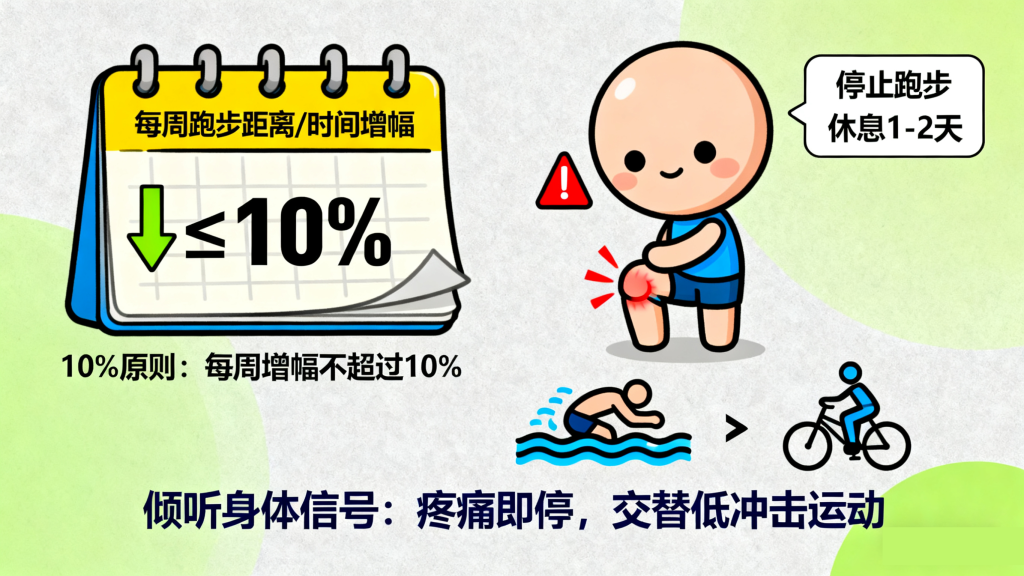

膝关节的适应能力需要逐步培养,突然增加运动量是“跑步膝”的主要诱因之一。遵循“10%原则”是关键:即每周跑步的距离、时间或频率增幅不超过10%,给关节和肌肉足够的适应时间。

同时,要学会“倾听身体的信号”:如果跑步时膝关节出现轻微疼痛,应立即降低速度或停止跑步;若疼痛持续,需休息1-2天,避免带伤跑步导致损伤加重。此外,建议交替进行“跑步+低冲击运动”(如游泳、骑行),让膝关节得到充分休息。